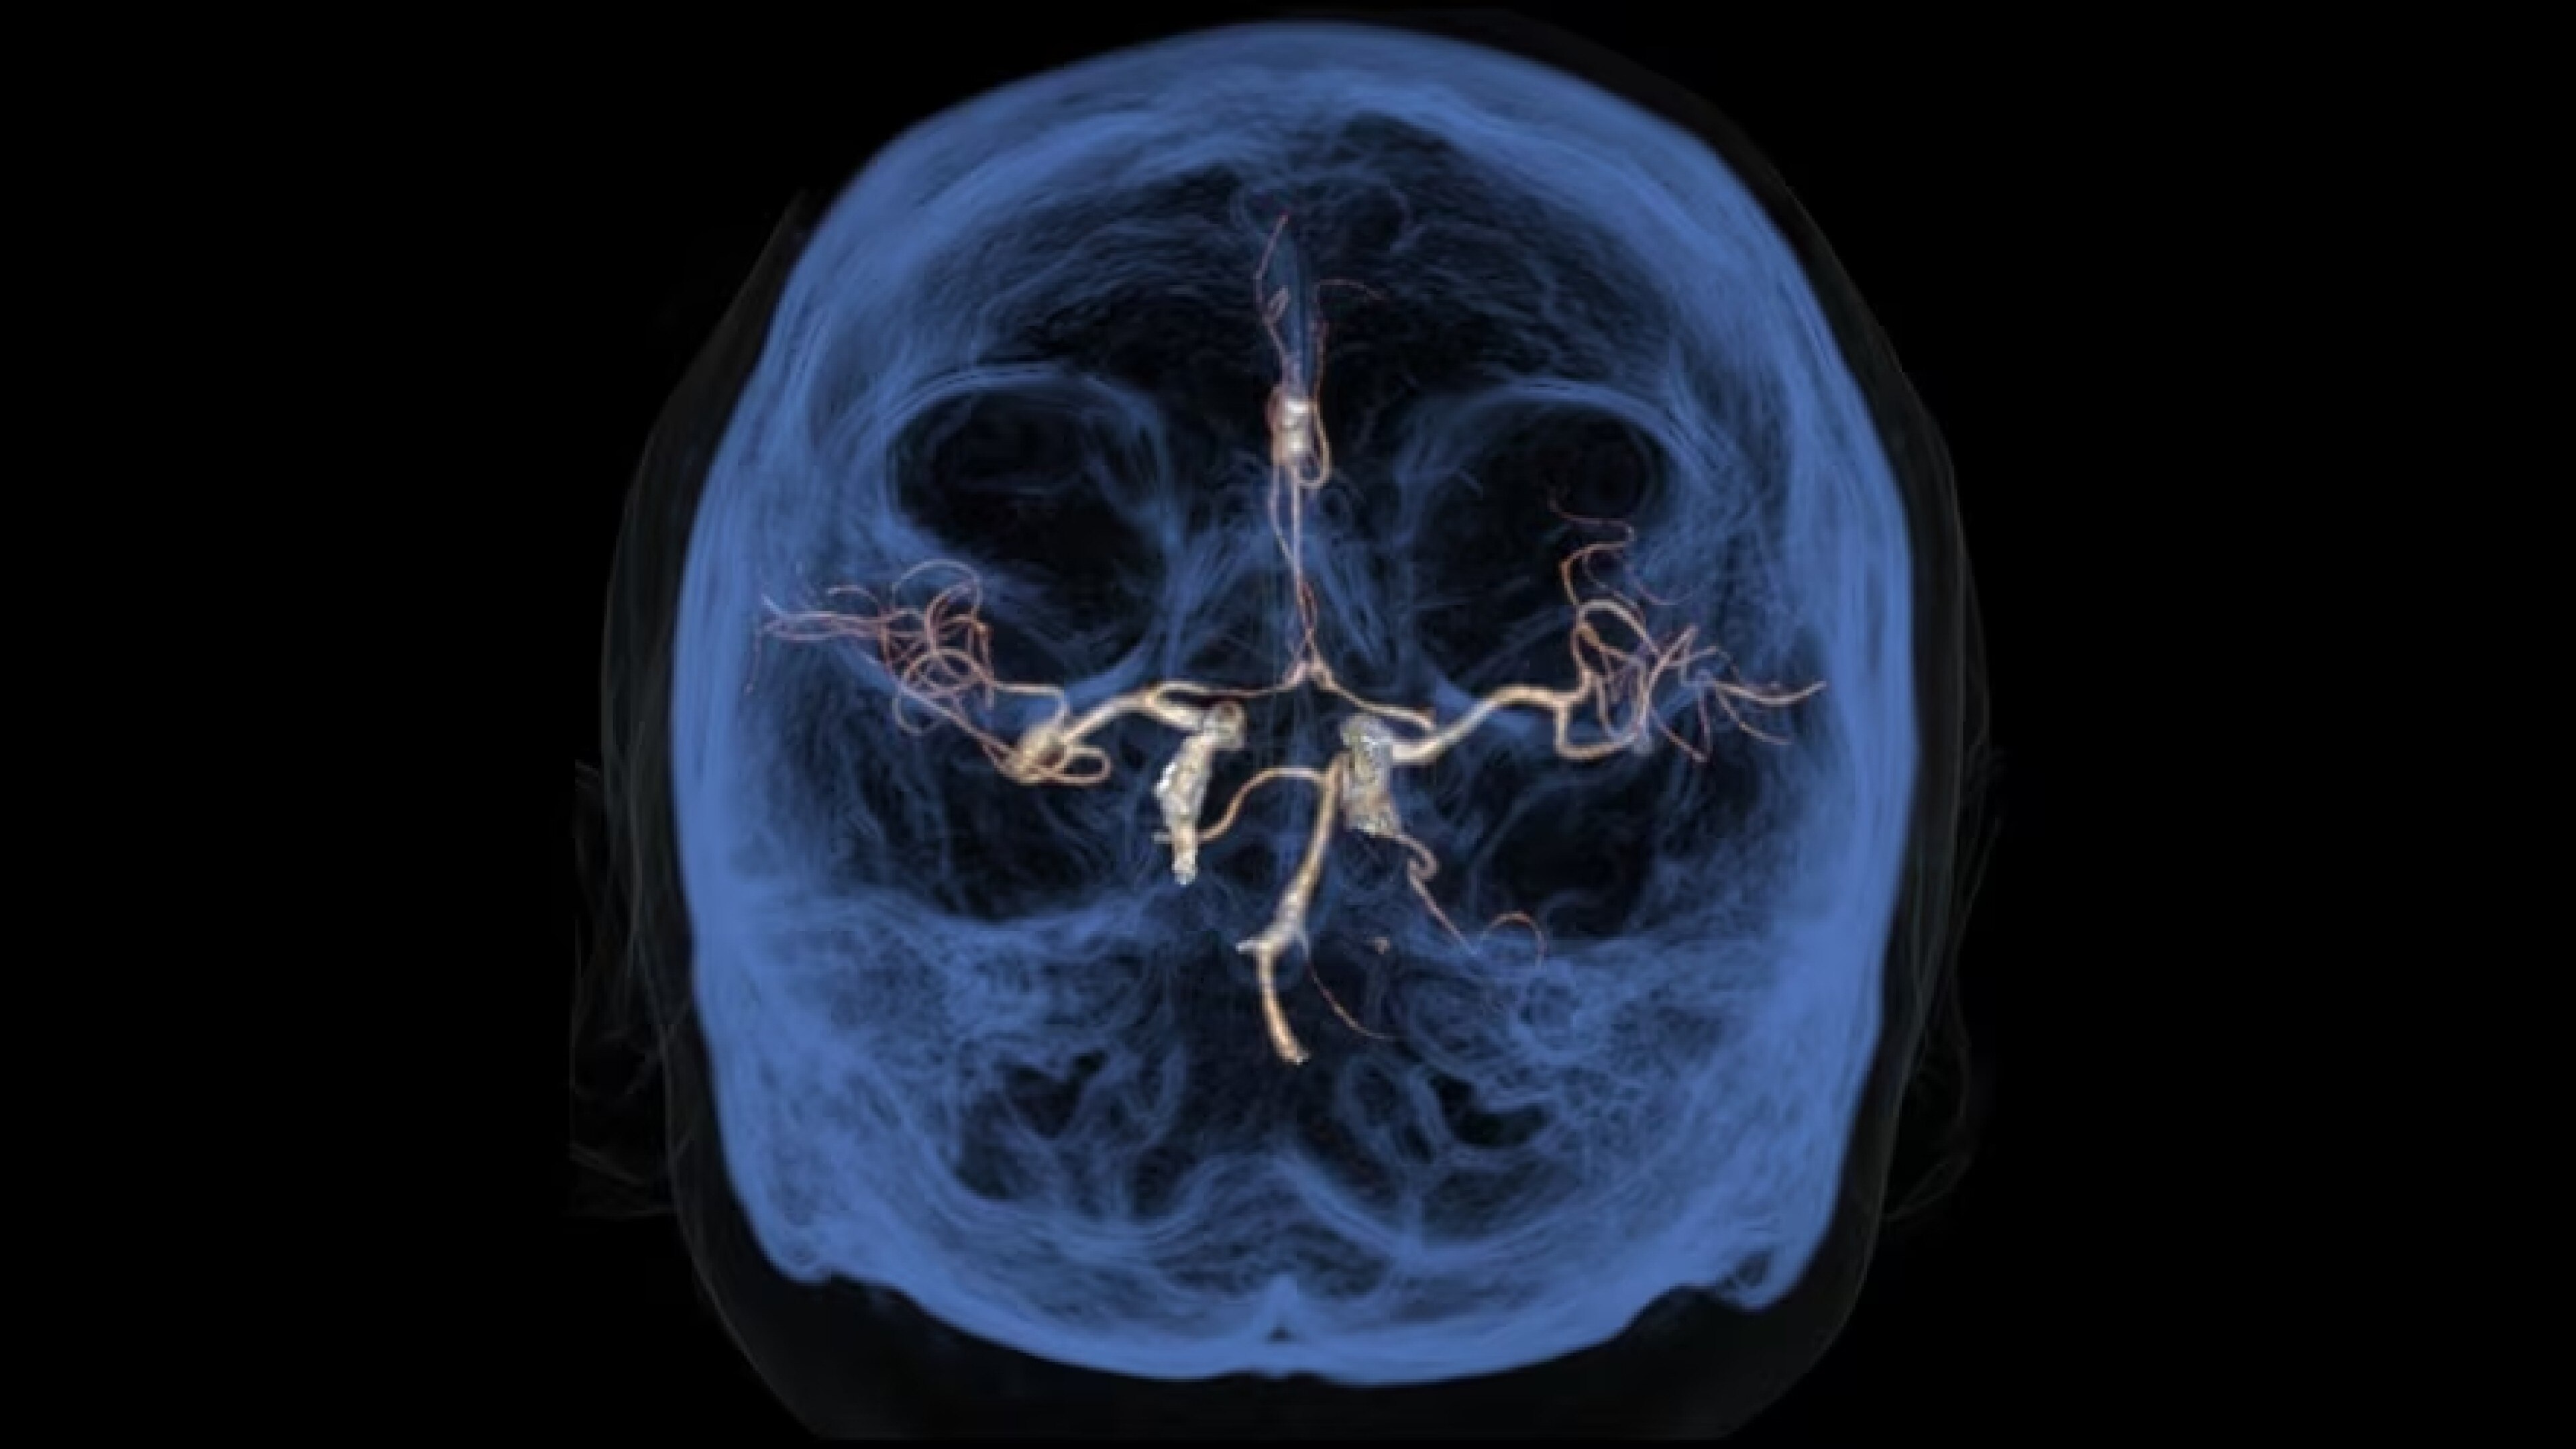

Autobone & VesselIQ Xpress

Fast and efficient vessel analysis from CT Angiography exams.

Zero-click bone segmentation and automated real-time fast tracking for all vasculature

• Zero-click bone segmentation for head, neck, and other anatomy.

• Automated real-time fast tracking for all vasculature.